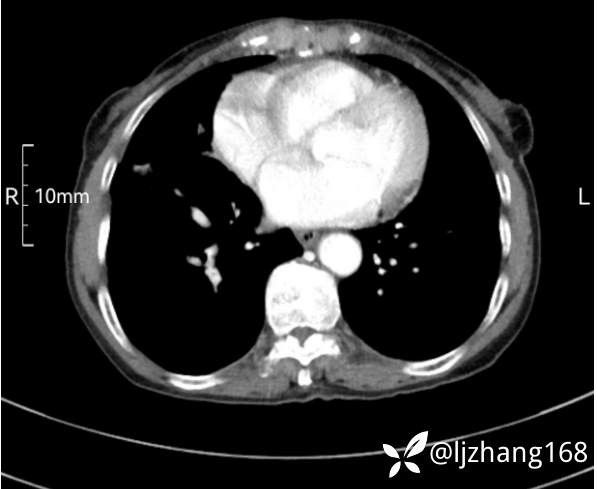

74岁女患,反复咳嗽2月,右肺空洞性病变,炎症OR肿瘤(有病理)

简要病史:2月前开始受凉后出现咳嗽,咳少许白色粘液痰,痰不易咳出,无痰中带血及咯血,无畏寒发热,外院胸部CT提示右下肺空洞病变,脓肿可能性大,常规抗感染治疗效果不佳。既往否认“糖尿病”等病史,有高血压基础病史,无吸烟史。

辅助检查:胸部CT右肺下叶前基底段结节并空洞

临床诊断:右肺空洞:脓肿?